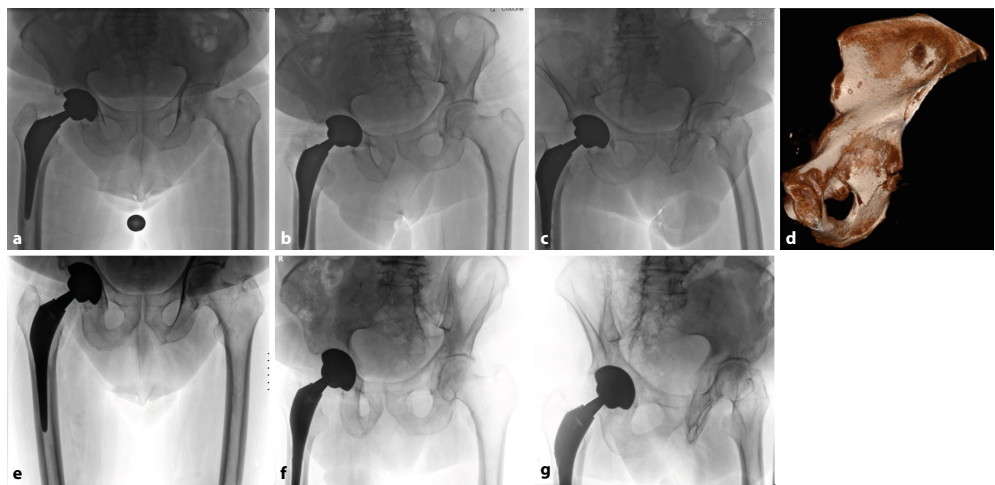

针对全髋关节置换术后日益增多的假体周围髋臼骨折(PPAF)这一复杂并发症,瑞士伯尔尼大学团队系统综述了基于Letournel分型的治疗策略。研究提出结合术前CT评估、AAOS/Paprosky分型及UCS分类的综合性诊疗路径,确立以植入物稳定性为核心的决策算法,为同时需要骨折修复和翻修技术的复杂病例提供了循证指导。